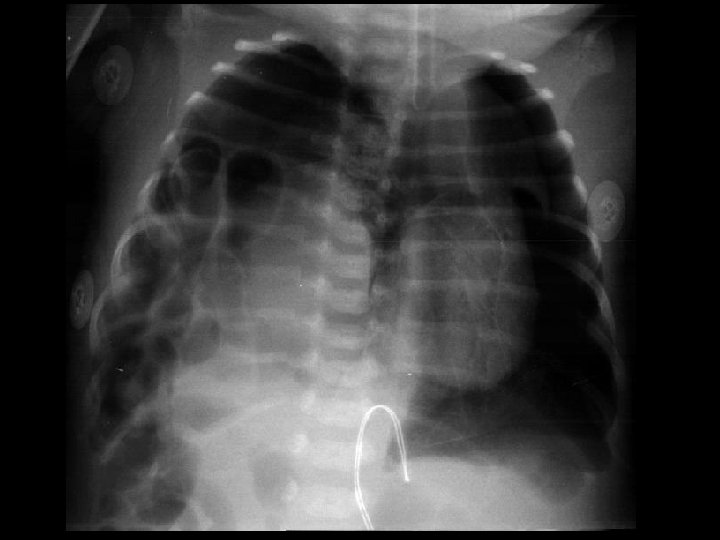

Case 2 Early Course • Trophic feeds re-started d 14 – Stopped on d 17 for abdominal distension – Prominent bowel loops, no pneumatosis – NPO for 7 days • Feeds re-started around d 21 • NPO again on 8/29 (d 30) for abdominal distension Jose Chavez CHO MR 960117

Case 2 Transfer • • • Transferred on 8/30 (1 month) for PDA ligation 800 g, systolic murmur, abdomen distended but soft NPO on HA PC/PS 17, PEEP 8, Rate 50 Multiple meds: – – – – Albuterol Pulmicort Caffeine Lasix Fluconazole Vancomycin Phenobarbitol Ativan Jose Chavez CHO MR 960117

Case 2 Radiology Evaluation • Upper GI – Flow through normal duodenum, duodenal-jejunal junction, jejunum • Contrast enema – Microcolon – Distended RUQ loops do not fill during enema • Small bowel follow-through – Opacification of distended loops Jose Chavez CHO MR 960117

Case 2 Radiology Diagnosis • Microcolon • Dilated ileum secondary to obstruction • Differential diagnosis: – Stricture – Adhesions – Meconium Ileus Jose Chavez CHO MR 960117